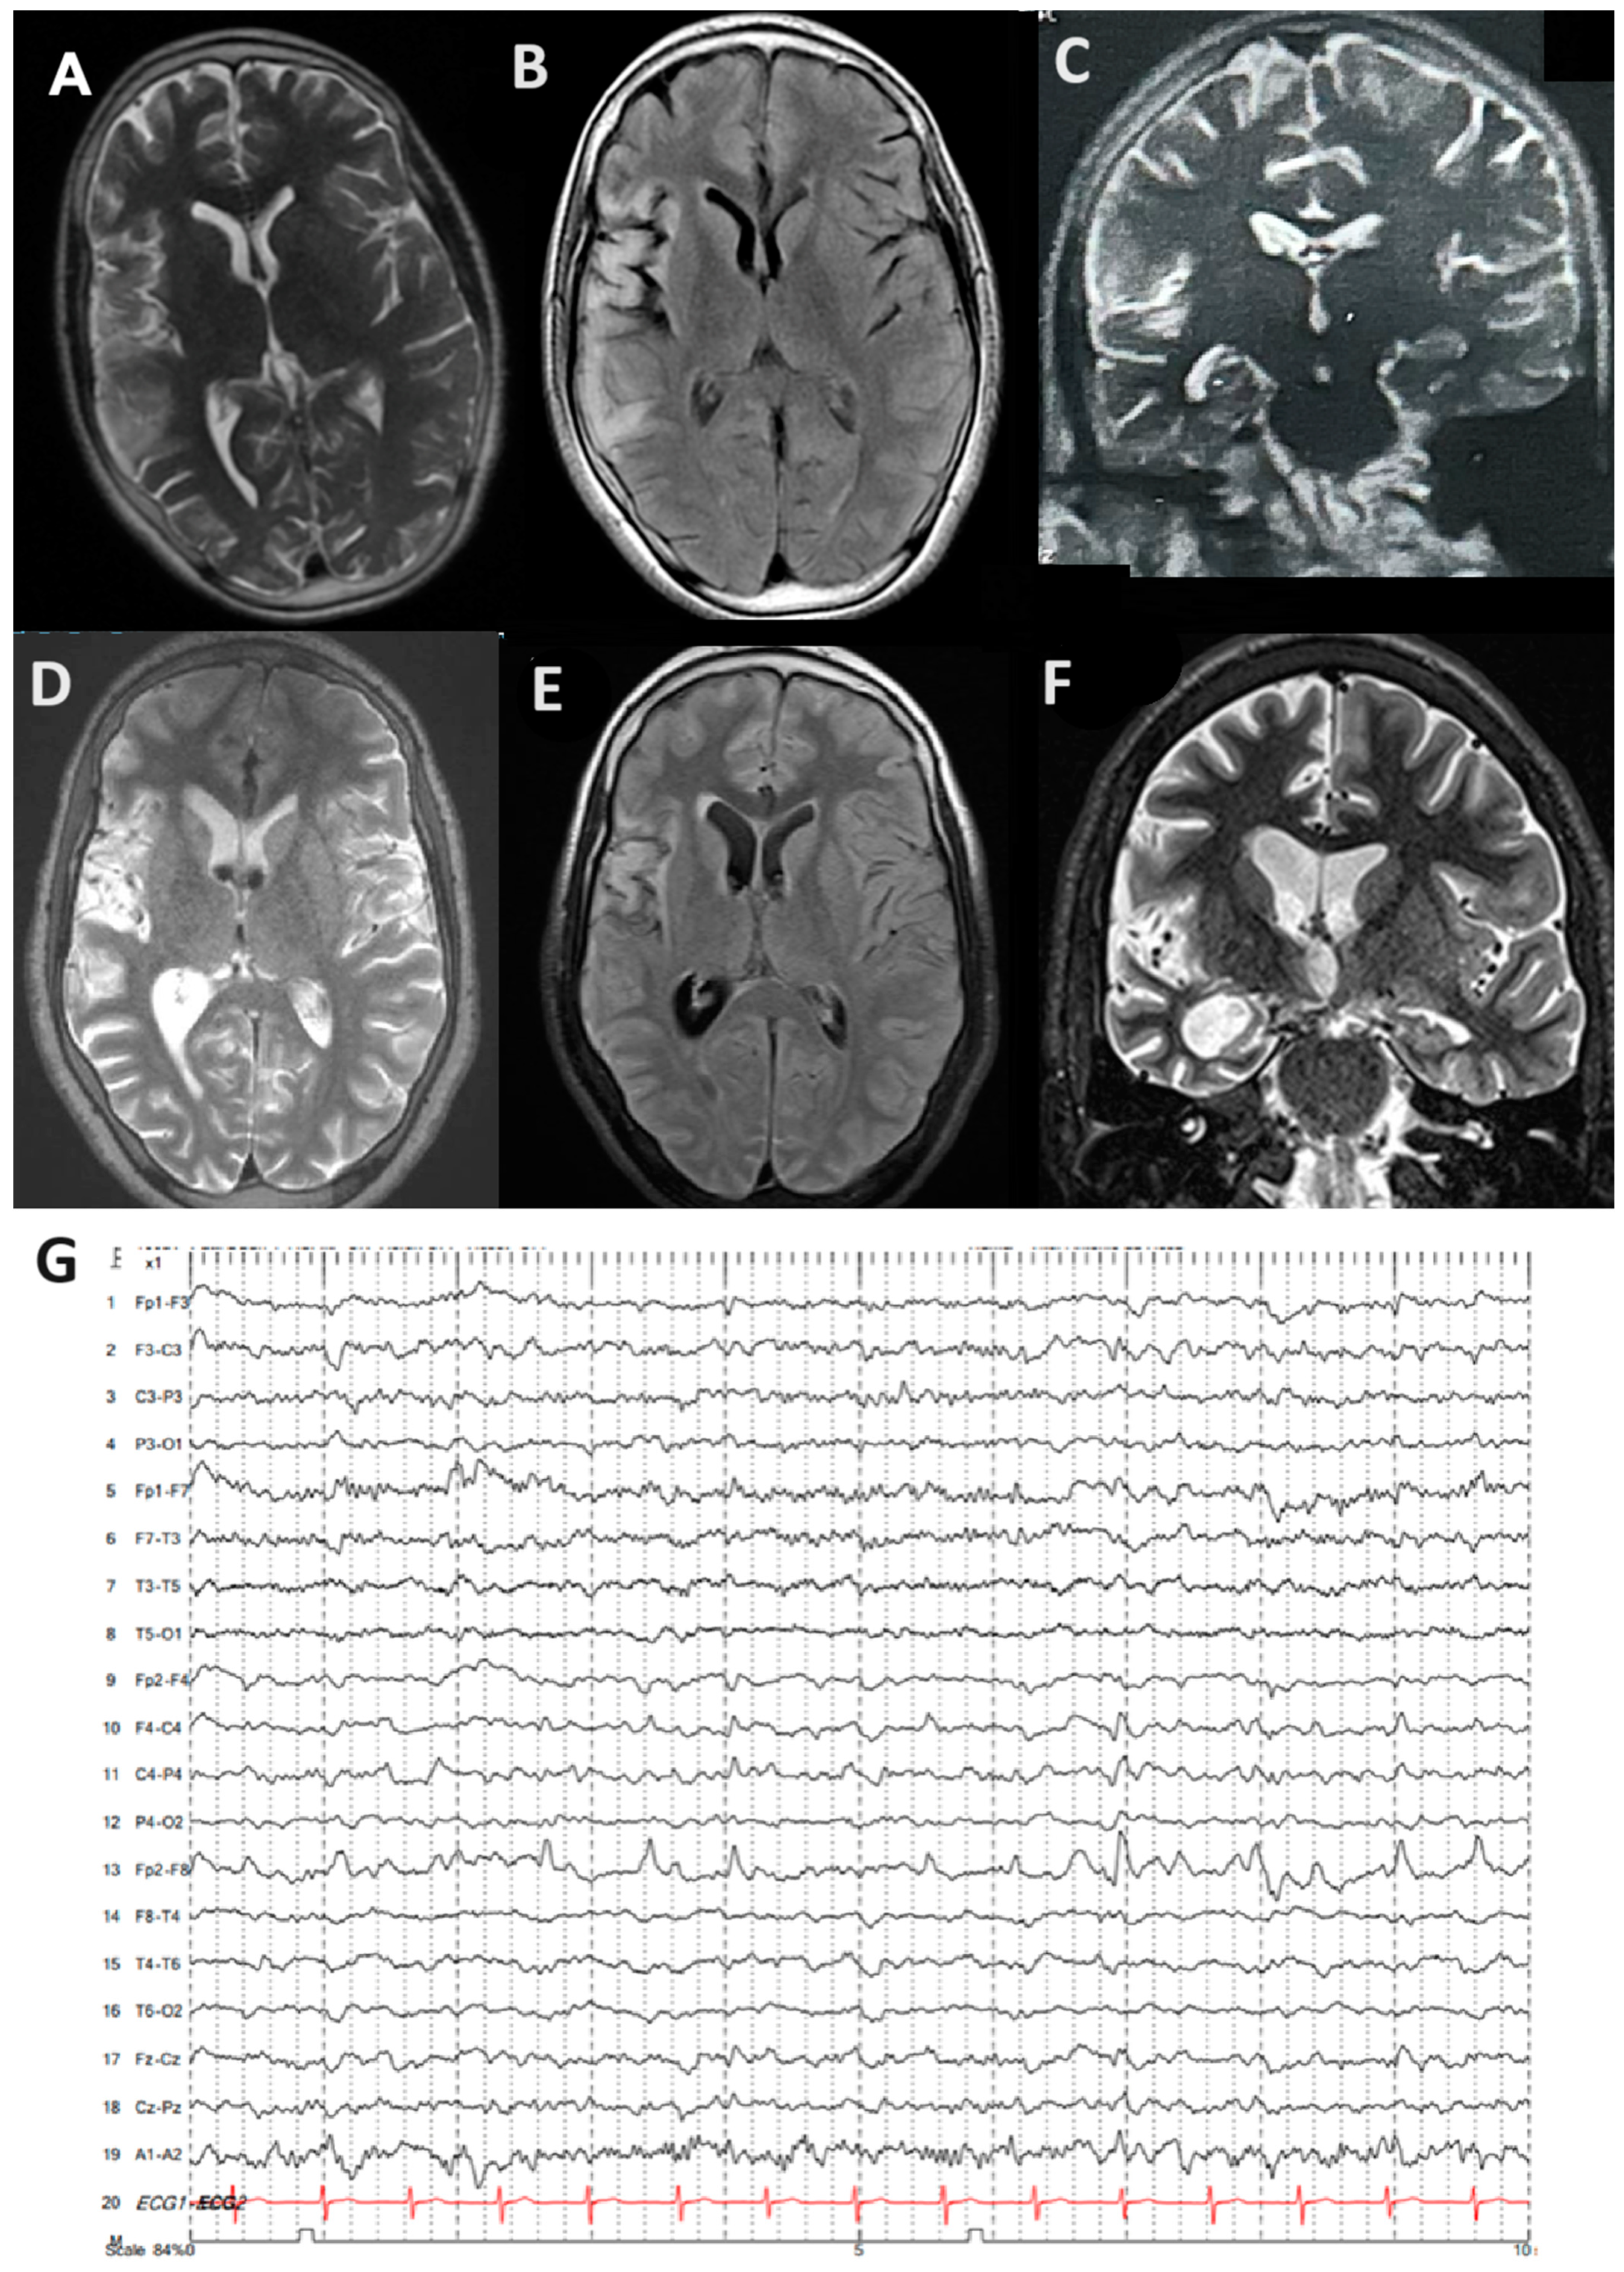

2. Case Report